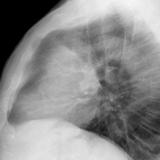

Case 8b Thymoma Lat

Date: 03/27/2009

Views: 14171